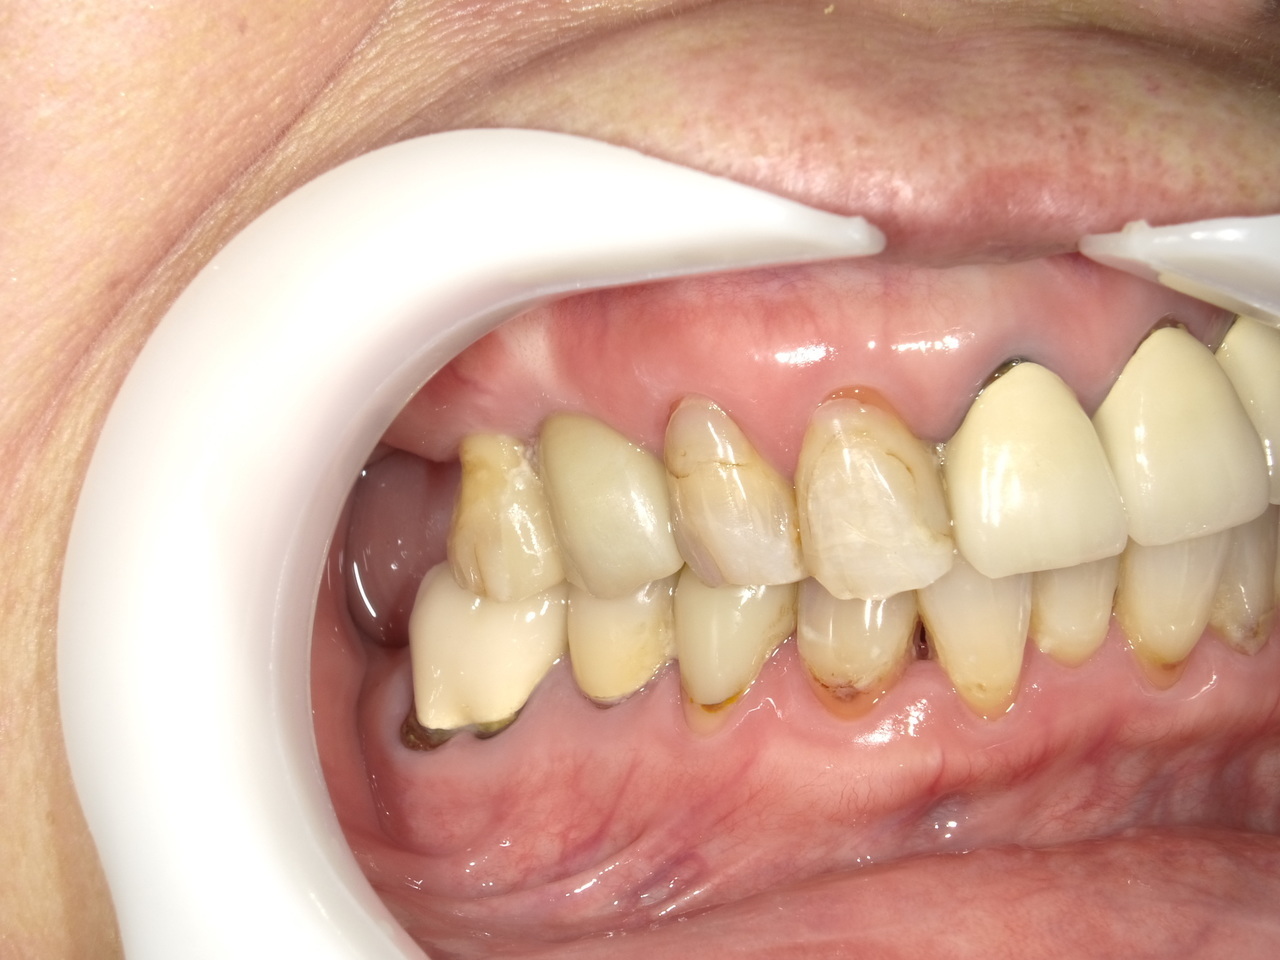

3.右上4番の著しい根露出と歯の周囲の骨の大きな欠損を伴った症例を2か月半で治療を終えたケース

M様 60代女性

症状としては、右上4番の根露出による動揺と疼痛がありました。

治療法としては、炎症が強いため、抜歯を行いました。その後、インプラント治療を希望されたため、インプラント埋入と、骨欠損部に人口骨を填入して、骨欠損部と歯肉の欠損部の回復を試みました。2か月後、歯肉の回復とインプラントの安定をみとめたため、デジタルにて印象を行い、2か月半後にインプラント上部ジルコニアを装着して治療を終えました。

治療結果としては、大幅な歯肉・骨欠損があったが、2か月半という短い期間での治療を完了することができ、かつ、十分な、歯肉も回復したため、ブラッシングしやすい環境を付与することができたため、インプラント周囲炎のリスクを軽減することができると考えます。

治療の期間・回数:約2.5か月、6回

治療の価格:352000円(税込)

治療費の内訳:インプラント基本料(フィックスチャー(メガジェン AnyOne使用)及び手術費用、投薬費用、レントゲン費用、インプラント上部費用(アバットメントおよびジルコニアクラウンの費用用)330000円(税込み)。人工骨費用 22000円(税込み)

治療のリスクや副作用:手術後に、痛みや腫れ、出血、合併症などを引き起こす可能性があります。噛む感覚がご自身の歯と異なる場合があります。見た目がご自身の歯と異なる場合があります。手術後にメインテナンスを継続しないと、インプラントが抜け落ちる可能性があります。